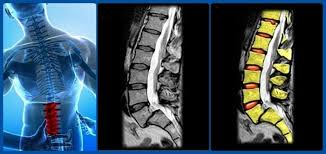

Omurgamızı oluşturan omur kemikleri birbirleri üzerinde bir düzen içeresinde dizilirler. Normalde omurların ön ve arka kenarları, bir alt ve bir üst omurun kenarları ile aynı hizadadır. Omurlar birbirlerine ön kısımda diskler arka kısımda faset eklemler yardımı ile bağlanır. Bu dizilimin dayanıklılığını arttıran bir çok bağ yapısı da kemikler arasında köprü oluşturur. Bel kayması olarak bilinen hastalıkta bir omur diğerinin üzerinde genellikle öne doğru yer değiştirir. Bu kayma olayı sonucunda, omurganın içinden geçen omuriliğimiz sıkışır ve her iki bacakta ağrı, uyuşukluk ve yanma gibi şikayetler meydana gelir. Beş çeşit bel kayması tipi mevcuttur. Bunlardan en çok karşılaşılanları, yaşlılıkta görülen dejenerasyona bağlı kaymalar, ameliyat sonrası gelişen kaymalar ve çocukluk çağında omurlardaki doğumsal sorunlara bağlı gelişen kaymalardır.

Bel kaymalarının tanısında radyografik testler çok önemlidir. Tedavi şeklinin belirlenmesinde kaymanın bel hareketleri ile artıp azalması hekimler açısından çok anlamlıdır. Bunun belirlenmesi hastaların öne ve arkaya eğilmesi sırasında çekilen radyografilerle sağlanır.

Stres kırıkları çoğunlukla düz radyografilerde saptanamaz. Şüpheli olguların bilgisayarlı tomografi incelenmesi uygun olacaktır. Kaymaya bağlı sinir sıkışmaları ve omurilik kanalındaki daralmaların tanısında MRI (Manyetik rezonans) çektirilmesi ile kesin tanı konulur. Doktorunuz gerekli durumlarda EMG (Elektromiyografi) testine de başvurabilir.